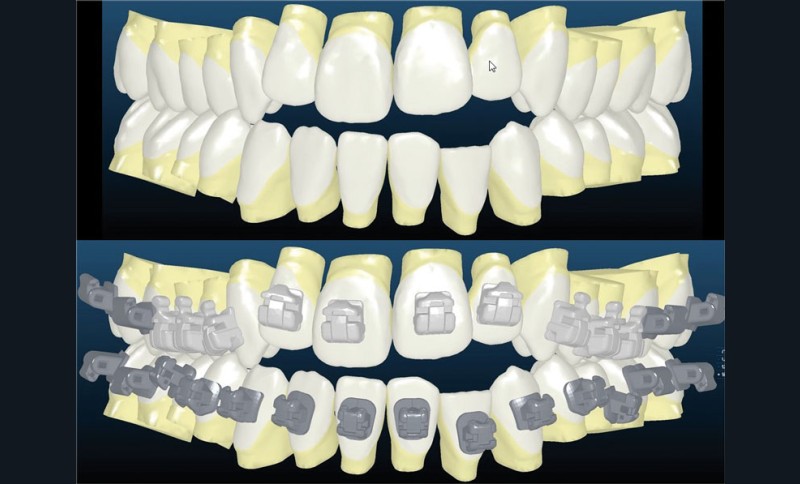

Le set up Insignia

Les empreintes ont été réalisées en sillcone wash technique et adressées au laboratoire Insignia. Actuellement, nous réalisons ces empreintes à l’aide de la caméra intra-orale Lythos et la fiche patient est initialement créée sur la caméra. Le transfert des empreintes au laboratoire est immédiat et le risque d’erreurs considérablement réduit (fig. 4 à 6).